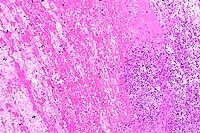

10x

obj

40x

- Case 24-4. Small intestine. Thickened, blunted villi

are expanded by abundant lymphocytes, macrophages, and fewer

eosinophils. The hypertrophic, vacuolated endothelium of a small

arteriole is infiltrated by lymphocytes and neutrophils.